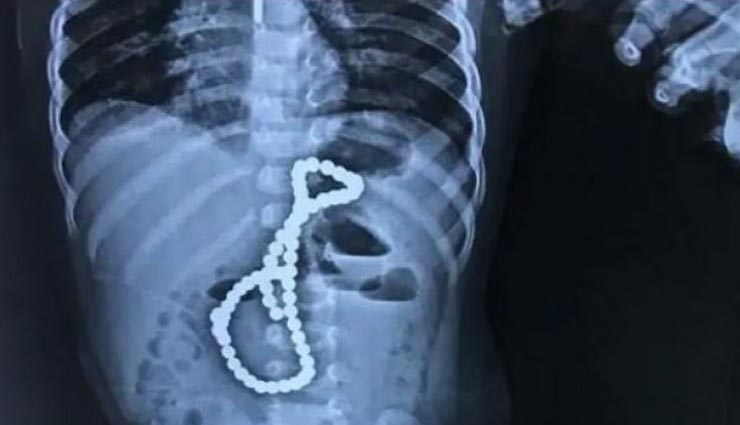

बच्चे के पेट में निकली ऐसी चीज जिसे देख डॉक्टर भी रह गए हैरान